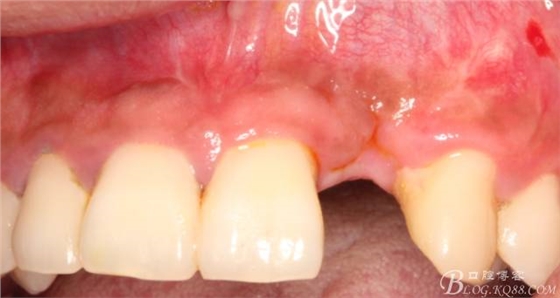

10天拆線一切正常,又過(guò)了兩周患者復(fù)診,自述期間無(wú)異常??趦?nèi)檢查,真的嚇了一跳,唇側(cè)鼓了個(gè)包,擠壓有白色分泌物溢出,絕對(duì)不是膿液,液體排除后,術(shù)區(qū)觸診空虛,外觀塌陷。這時(shí)候考研大夫的時(shí)刻到了,是先觀察一段時(shí)間再說(shuō)?還是馬上進(jìn)行處理?我的回答是:馬上處理!如果你沒(méi)有及時(shí)處理,而是放患者回家觀察,那么接下來(lái)會(huì)發(fā)生如下情況:1.回家后患者家屬及親友會(huì)有很多你可以想象得到的討論;2.患者及家屬會(huì)對(duì)你產(chǎn)生不信任,勢(shì)必會(huì)到其他門(mén)診或醫(yī)院檢查,他院大夫會(huì)不會(huì)發(fā)表對(duì)你不利的言論;3甚至?xí)蚁嚓P(guān)法律界人士找你討要說(shuō)法。